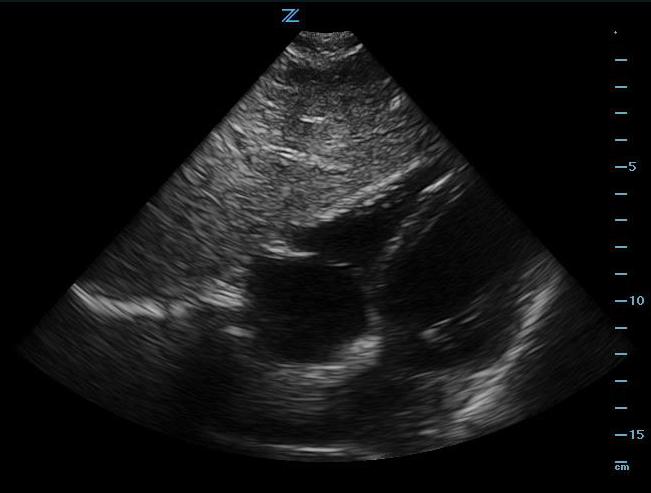

Subxiphoid Four-Chamber View

- Place the probe in the subxiphoid region with the transducer indicator toward the patients’ right side or right shoulder. Angle the probe toward the left shoulder.

- This view shows the right ventricle immediately adjacent to the left lobe of the liver. (Figure 2, Video 1) A pericardial effusion will be easily recognized between the liver and the heart. (Video 2)

- Increasing the depth of the image, applying more pressure, and having the patient take a deep breath will improve chances of obtaining a good image.

- Figure 2. Subxiphoid view